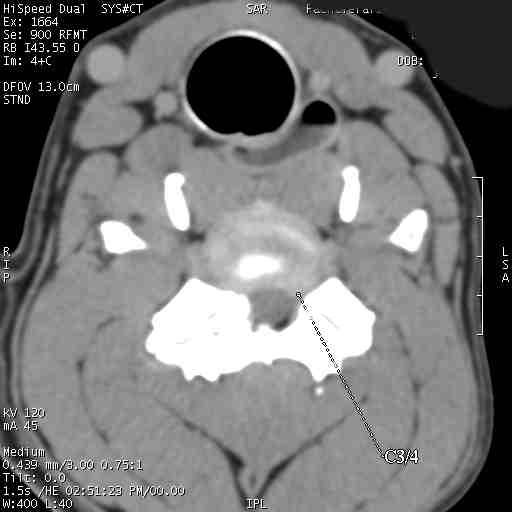

Im folgenden Beispiel sieht man computertomografische Bilder der Halswirbelsäule einer Dogge mit folgender Diagnose: Knöcherne Stensoe C3/4 [= 3./4. Halswirbel], sanduhrförmige Kompression des Myelons auf der Höhe C3/4, Bandscheibenvofall C6/7 [= 6./7. Halswirbel], Myelon mit seitlicher Abweichung nach links : Im Ergebnis eine Halswirbelstenose an den beiden Stellen mit Kompression des Myelons, die zu den Lähmungserscheinungen führt.